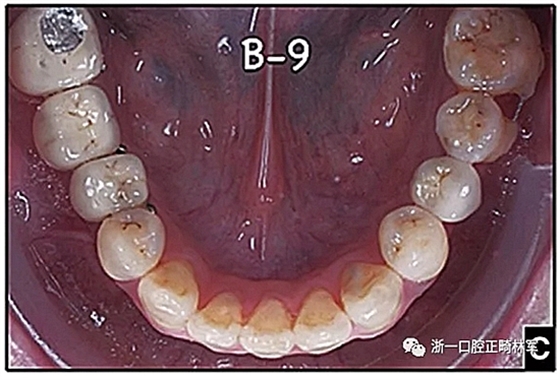

圖15.A,去除固定裝置一個(gè)月后,下頜左側(cè)第二前磨牙復(fù)發(fā),移動(dòng)到種植體愈合的部位; B,B-0表示開(kāi)始再治療,通過(guò)鏈圈和推簧的矯正復(fù)發(fā); C,B-9是治療結(jié)束后3個(gè)月回訪時(shí)下頜弓的咬合面觀,這是再治療階段的9個(gè)月。下頜左側(cè)第二前磨牙和第三磨牙的頰面粘合一個(gè)固定保持器,以防止復(fù)發(fā)。